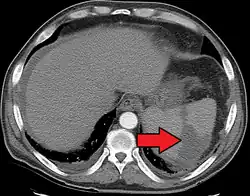

Splenic infarct seen on CT

An abdominal CT scan is the most commonly used modality to confirm the diagnosis,[3] although abdominal ultrasound can also contribute.[5][6][7]